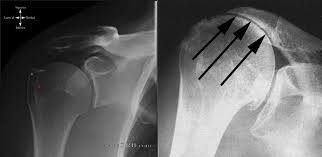

Rotator Cuff Tear Arthropathy Occurs after long-standing large rotator cuff tears The humeral head moves upward due to lack of tendon support Leads to severe arthritis and weakness

- X-rays

- Joint space narrowing

- Bone spurs

- Joint deformity